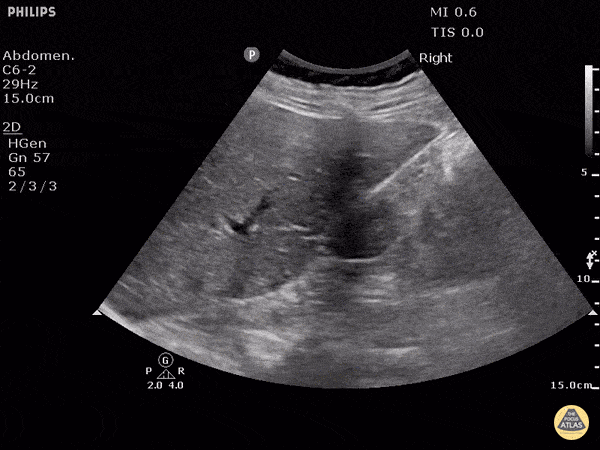

What view is this?

The subxiphoid/subcostal view is the primary echocardiography view used in the FAST exam to obtain a quick view of the heart. The other views might be used in further examination of the heart, if warranted or if the subxiphoid view is for some reason not accessible.